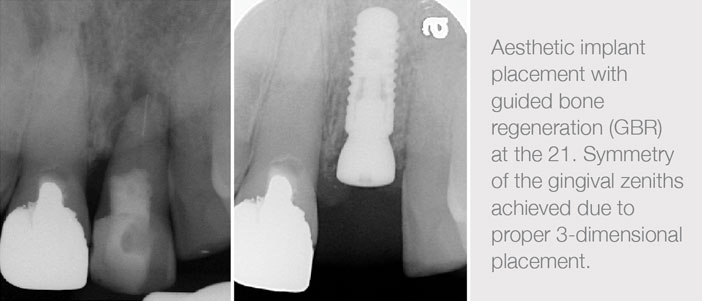

The patient above presented with a failing right central incisor (21). The tooth was extracted with an atraumatic technique and due to the presence of the infection, the socket was carefully curetted and allowed to heal for 8 weeks. A protocol for type II placement (early placement within 4-8 weeks of the extraction) was chosen as this would permit predictable augmentation of the buccal hard tissue. The implant was allowed to heal via primary wound close and was exposed after 3 months via a pedicle flap. The crown was fabricated 1 month later. The patient was happy with the final result.